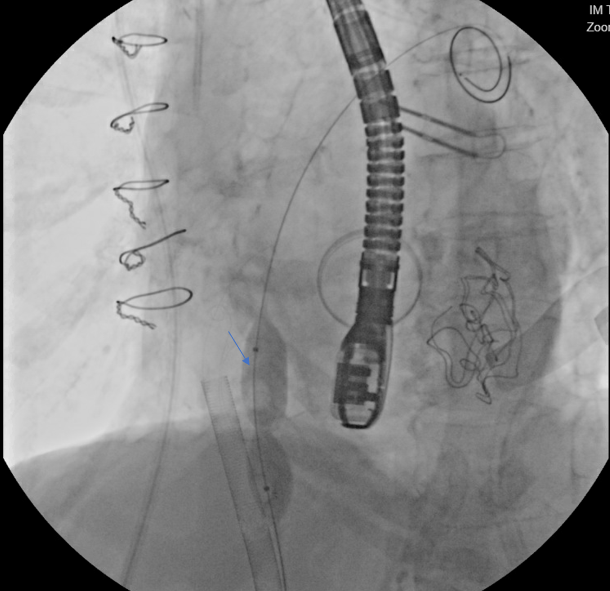

We performed transseptal puncture using Versacross wire (Baylis Medical) and Baylis catheter, followed by septostomy using a 14 mm Armada balloon (Abbott) (Figure 3). We then advanced the AlphaVac system (Angiodynamics) to the left atrial and directed the tip of the funnel towards the thrombus (Figure 4), which was successfully removed after multiple runs of aspiration using the AlphaVac system. (Figure 5A, B). The system was then removed, and the femoral venous access was closed using Perclose (Abbott). The patient was transferred to the cardiothoracic intensive care unit for further monitoring. Unfortunately, after transfer, a stroke occurred in the patient’s right middle cerebral artery. Her goals of care were discussed with the family, and she was transitioned to comfort care. She died 3 days post-procedure.

Our case illustrates that migration of left atrial thrombus can occur, and may lead to mechanical mitral valve obstruction and cardiogenic shock.1,2 Transcatheter procedures of the left-sided cardiac structures using the transseptal approach have evolved over the past several years, expanding the range of transcatheter structural heart interventions.3 Mechanical aspiration of left-sided cardiac thrombus using the AngioVac device system (AngioDynamics) has been reported in the literature.1,2,4 The AlphaVac device allows mechanical aspiration of the thrombus without the need for perfusionist support. In our case, we demonstrate the utility of the AlphaVac device system for left atrial thrombectomy of a large thrombus strand that migrated from the LAA and caused cardiogenic shock due to mechanical mitral valve obstruction.